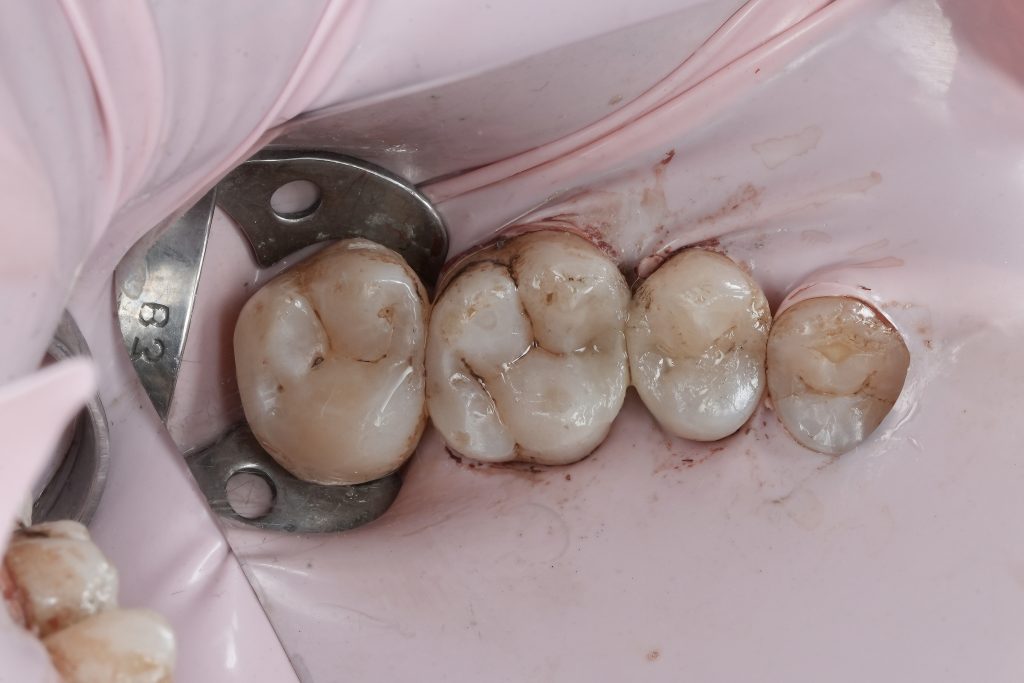

Matrix System and Proximal Control

A sectional matrix system with controlled separation was used to recreate natural proximal anatomy. Proper matrix adaptation allowed:

- Accurate emergence profile

- Tight, functional proximal contact

- Correct contour without overhangs

Wedges were placed to seal the gingival margin and provide slight tooth separation for predictable contact formation.

Composite Placement

Composite was placed incrementally using an anatomic layering approach:

- Initial proximal wall build-up to establish contact

- Incremental dentin replacement

- Final enamel contouring to reproduce natural morphology

Each increment was carefully adapted and polymerised to minimise shrinkage stress and marginal gaps.